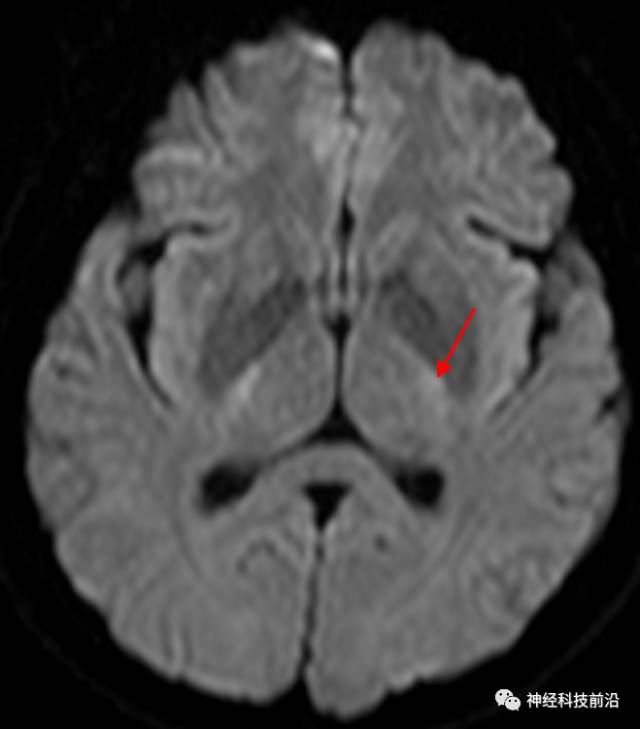

终上所述:脑干高信号为一近环形纤维束,内囊后肢高信号为皮质脑桥束,皮质脊髓束在中脑位置略靠后。高信号位于中脑前缘,是皮质脑桥束的位置所在,另外有部分桥连纤维。